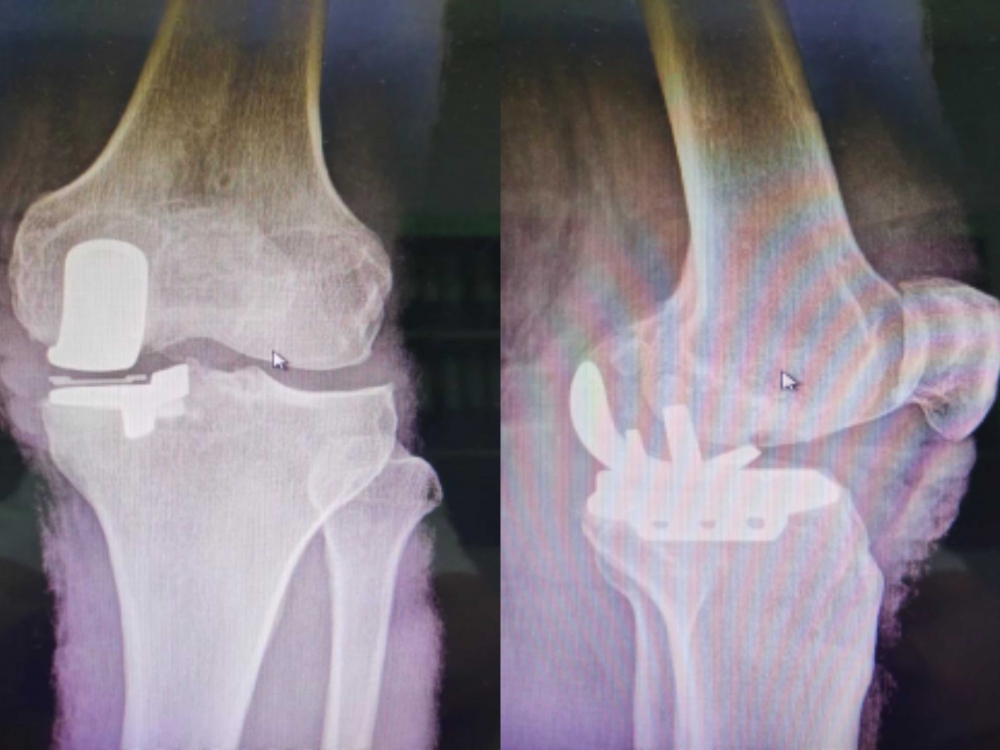

術(shù)后

與全膝置換術(shù)相比,膝關(guān)節(jié)單髁置換術(shù)切口更小,膝關(guān)節(jié)內(nèi)損傷更小,患者術(shù)后恢復(fù)更快,而且由于膝關(guān)節(jié)的韌帶得到保留,患者術(shù)后的膝關(guān)節(jié)活動(dòng)度和本體感覺(jué)更好。